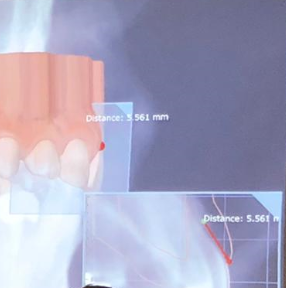

A Medit i500 scan was taken and merged with a CT scan and the distance to bone was measured (5.5 mm’s) giving enough space for soft tissue contouring with a diode laser. The 3D X-ray must be captured with cotton rolls placed in the vestibule so that you can differentiate between the gingiva and the lip. Ideally you should not close the base of the digital model by the intra-oral scanner as it can make the merge of the data sets more difficult than it needs to be.

A Medit i500 scan was taken and merged with a CT scan and the distance to bone was measured (5.5 mm’s) giving enough space for soft tissue contouring with a diode laser. The 3D X-ray must be captured with cotton rolls placed in the vestibule so that you can differentiate between the gingiva and the lip. Ideally you should not close the base of the digital model by the intra-oral scanner as it can make the merge of the data sets more difficult than it needs to be.